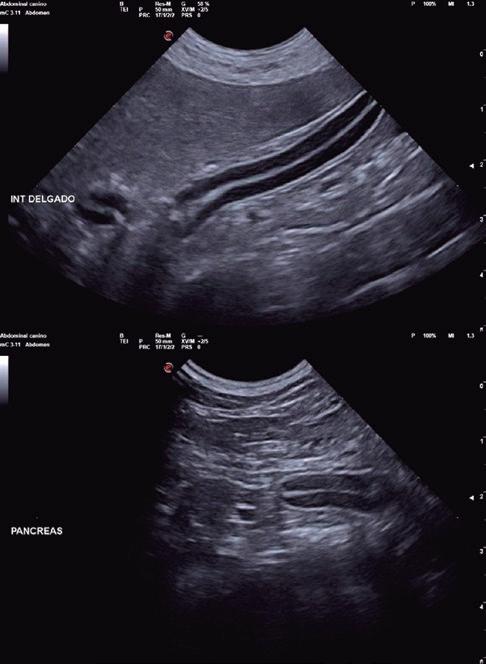

Bloqueantes de canales del calcio Hidralazina, nitratos e IECA